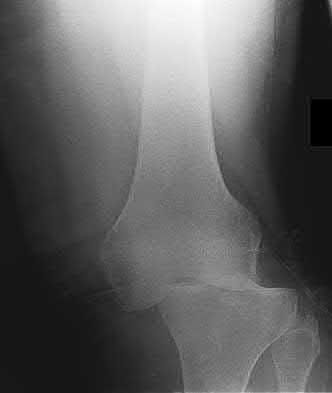

1010) Figures 66a through 66d are the radiographs and CT scans of a 72-year-old woman with osteoporosis who sustained a fall from standing height. She has pain and is unable to bear weight on the right knee. Surgical management is considered. Which of the following best describes the preferred proximal screw fixation construct within a laterally applied buttress plate?

5. 6.5-mm partially threaded cancellous screws Corrent answer: 2

Displaced split depression fractures of the lateral tibial plateau require articular surface elevation, restoration of anatomic plateau width, and sustained elevation of the reduced articular components. This is accomplished by introducing nonlocking lag screws first to compress and narrow the lateral rim thus restoring plateau width. The introduction of locking screws first would disallow compression and accordingly prevent reduction of the lateral rim.

Locking screws are inserted after the lag screws if the bone is osteoporotic to maintain articular elevation. Several biomechanical studies have demonstrated

inferior performance of large implants (6.5-mm screws and 4.5-mm plates) with regard to sustaining joint surface elevation.